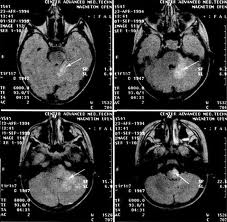

Доброкачественная лимфоцитома, или лимфаденоз кожи (lymphadenosk benigna ciihs), представляет собой опухолеподобное уплотнение, обычно на мочке уха, в области соска молочной железы или мошонки (наиболее частые локализации) и иногда на других участках кожи. В этот период могут возникать неврологические симптомы, включающие поражение как центральной (менингит, энцефалит. миелит, энцефалопатия), так и периферической (краниальные невропатии, радикулопатии, периферическая нейропатия, множественные мононевриты, плечевая плексопатия, пояснично-крестцовая плексопатия, Гийена Барре-подобный синдром, моторная нейропатия и ) нервной системы. Для поражения сердца характерны нарушения ритма и проводимости (атриовентрикулярные блокады), редко обнаруживают субклинически протекающий мио- и/или перикардит.

Поздняя стадия заболевания. Для поздней стадии болезни Лайма характерно поражение кожи по типу хронического атрофического акродерматита относительно редкого заболевания с вовлечением разгибательных поверхностей дистальных отделов конечностей. Начало процесса - инфильтративно-воспалительная фаза, за которой через годы следует атрофическая фаза. Иногда происходит присоединение склеротического процесса, очень напоминающего склеродермию. Среди других проявлений поздней стадии полинейропатия, прогрессирующий энцефаломиелит.